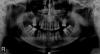

Sofiba Опубликовано 24 января, 2011 Поделиться Опубликовано 24 января, 2011 Уважаемые врачи очень прошу Вашей помощи!!!!!Со своей фобией, сильнейшей боязнью лечения зубов, оказалась в ужаснейшей ситуации из которой, пока не могу найти выход.Мои зубки на ОПГ, если надо что-то еще для Вашего совета, пожалуйста скажите, выложу.Моя проблема в том, что я могу все делать только под наркозом. Даже осмотр просто с зеркалом несколько проблематичен. Зубы в ужасном состоянии, уже пару лет как не улыбаюсьСейчас мне предлагают 2 варианта:1) Удалить большинство верхних зубов и 2 нижних, залечить кариесы, почистить и поставить съемные протезы что конечно же ужасно угнетает.2) Удалить 3-4 зуба и поставить циркониевые коронки и мосты, там где не будет зубов. Первый вариант, видя меня, в 3-х клиниках мне сказали, что это мое единственное решение и протезировать под наркозом не берутся.Второй вариант, озвучили в 2-х клиниках. При этом на вопрос, какие манипуляции надо делать в живую, ответы очень расплывчатые и все заканчивается словами, что бояться не надо, больно не будет и все основные моменты будут сделаны под наркозом. Но я всего боюсь взять себя в руки, как об этом просят, при все своем большом желании не смогу Конечно, совсем не хочется в 34 года заиметь съемные протезы, но и очень боюсь оказаться с оплаченными коронками, которые невозможно поставить. Что мне делать?!!!! Действительно ли возможно протезирование под общей анестезией? И как себя ведут циркониевые коронки и мосты, могут ли не беспокоить 5-10 лет, пока на что-то новое денег не накоплю? А может есть еще какой выход в моей ситуации? Ссылка на комментарий

pawa Опубликовано 24 января, 2011 Поделиться Опубликовано 24 января, 2011 На снимке много зубов уже с удалёнными нервами, это лечение было под наркозом? Ссылка на комментарий

Sofiba Опубликовано 25 января, 2011 Автор Поделиться Опубликовано 25 января, 2011 А у меня только снимок, который выше в первом сообщении А что нужно еще сделать? Ссылка на комментарий

Alexandr dantist Опубликовано 25 января, 2011 Поделиться Опубликовано 25 января, 2011 А у меня только снимок, который выше в первом сообщении А что нужно еще сделать? ссори,спешил к пациенту, описАлся Структуры корня там достаточно, на я бы сделал одиночные коронки. Мост на зубах после резекции будет "условно надежный"... Ссылка на комментарий